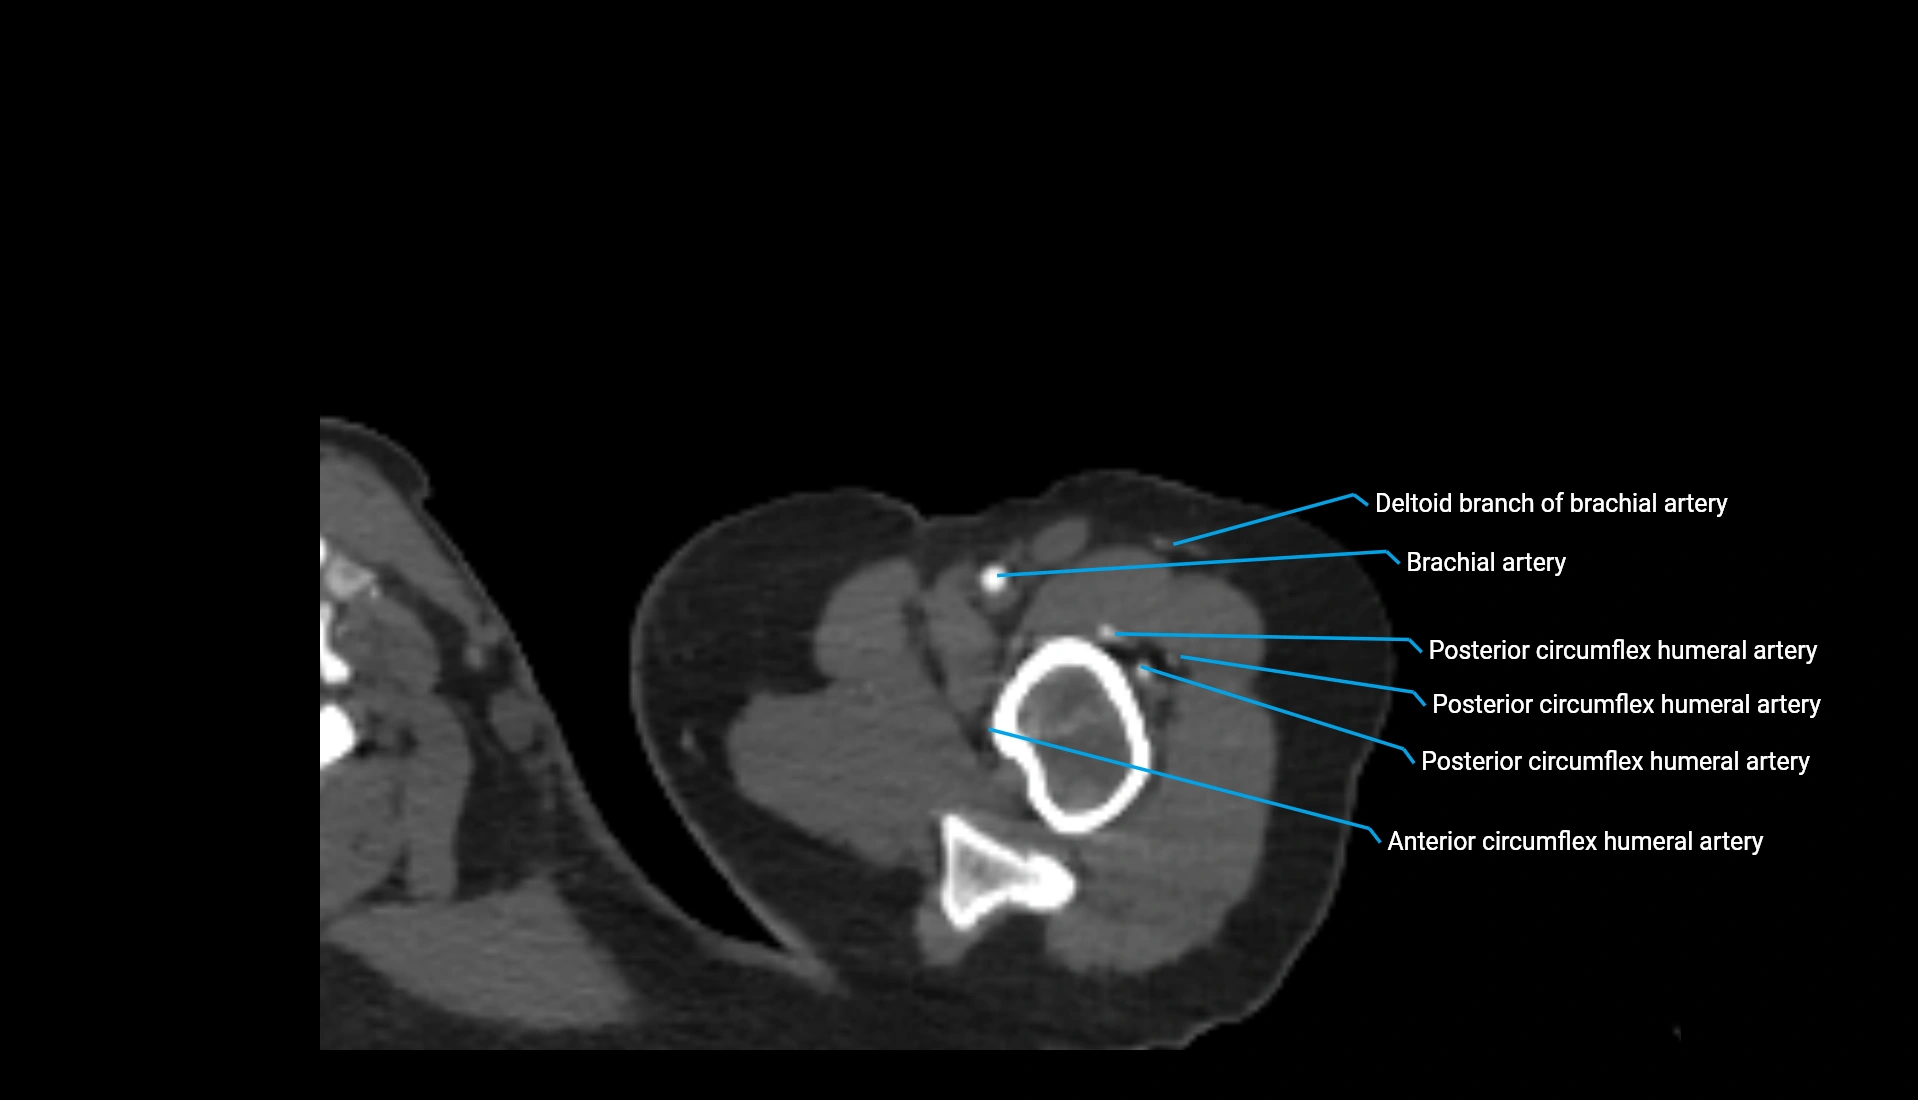

CT Appearance

Non-Contrast CT:

• Cortex: High-density, sharply defined

• Subchondral bone: Dense cancellous matrix

• Articular surface: Smooth concave contour articulating with the capitellum

• Excellent for evaluating bone integrity, alignment, and subtle fractures